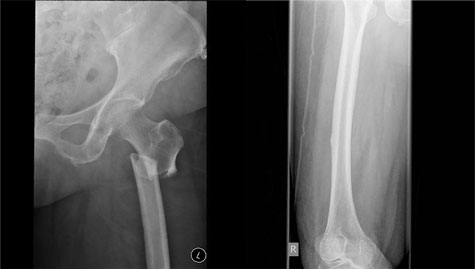

Box 1 – Bilateral atypical femoral fractures in an older woman after bisphosphonate therapy for 9 years*

* Note the characteristic findings of a predominantly transverse fracture line, periosteal callus formation and minimal comminution on the left, and the periosteal reaction on the lateral cortex on the right femur, indicating an early stress fracture.

Atypical femur fractures. Clinical trial data clearly support the beneficial effect of bisphosphonates in preventing minimal trauma fractures. However, oversuppression of bone remodelling may allow microdamage to accumulate, leading to increased bone fragility.51 Cases of AFF and severely suppressed bone remodelling after prolonged bisphosphonate therapy52 have prompted further research and recent guideline development.53 However, this finding is not universal. AFFs occur in the subtrochanteric region or diaphysis of the femur and have unique radiological features, including a predominantly transverse fracture line, periosteal callus formation and minimal comminution, as shown in Box 1.53 AFFs have been reported in patients taking bisphosphonates and denosumab, but about 7% of cases occur without exposure to either drug. AFFs appear to be more common in patients who have been exposed to long term bisphosphonate therapy, with a higher risk (113 per 100 000 person-years) in patients who receive more than 7–8 years of therapy.53 Although many research questions remain unanswered, including aetiology, optimal screening and management of these fractures, the risk of a subsequent AFF is reduced from 12 months after cessation of bisphosphonate treatment.